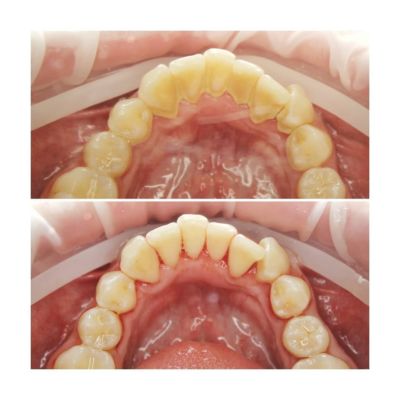

Zdjęcie pokazuje zęby przed i po scalingu.